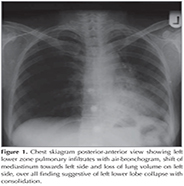

General physical and systemic examination revealed nothing abnormal except fine crepitations in left infra-scapular and infra-axillary region. Laboratory investigations were within normal limits. Pulmonary function test was normal without signs of bronchial obstruction and sputum was negative for acid fast bacilli. Her chest skiagram PA view showed left lower zone infiltrates with air-bronchogram, loss of lung volume on left side and same side shifting of mediastinum, over all finding suggestive of left lower lobe collapse with consolidation (Figure 1). Contrast enhanced chest tomography (CECT) scan of chest showed loss of lung volume on left side with lower lobe cicatricial collapse and consolidation with air-bronchogram while the scanogram revealed a small bud like projection on left para tracheal region, at the level of the thoracic inlet (arrow) (Figure 2A,B). The presence of a narrow stalk connecting the lesion with the posterior wall of the trachea was critical in establishing the diagnosis of a tracheal diverticulum. Furthermore, three-dimensional reconstruction CT ?virtual bronchoscopy confirmed our diagnosis as it showed an orifice of tracheal diverticulum in tracheal wall on left side just below the vocal cord (Figure 3). Fiber optic bronchoscopy (FOB) showed air bubbles and secretions coming out from an opening in the postero-lateral wall of trachea on left side approximate 1 cm below the vocal cords (Figure 4A, B). Further FOB revealed marked narrowing of the left lower lobe bronchus suggestive of cicatricial collapse. The diagnosis of tracheal diverticulum with left lower lobe collapse was made. The barium contrast study performed to look for any esophageal communication, but to fail (Figure 5). Bronchoalveolar lavage taken during FOB, sent for gram stain and pyogenic culture. Patient was referred for surgical management looking at the frequency of symptoms, but she denied for any operative intervention. She was then managed conservatively with antibiotics, mucolytics and vaccinations to reduce the frequency of chest infections and subsequent complication.